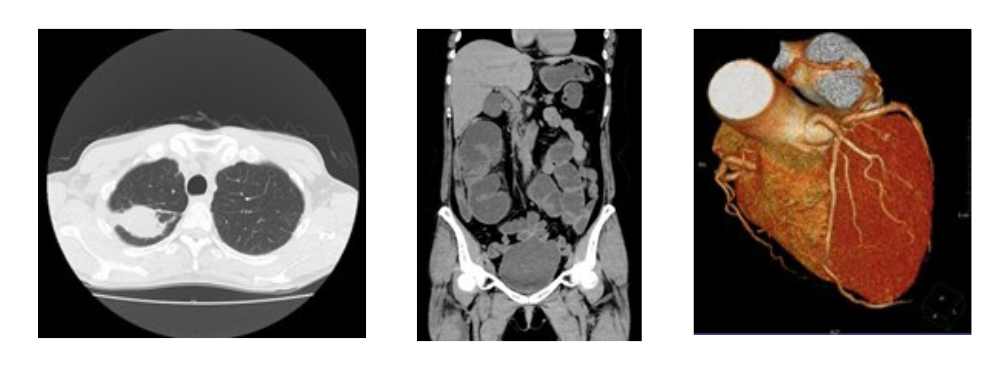

【胸部】 【腹部】 【心臓】

マルチスライスCTでは頭部・胸部・腹部・下肢など全身の撮影ができます。3次元の情報により様々な断面の画像や3D画像を作成することができます。これにより病変の描出もしやすくなり、「がん」などの早期発見にもつながります。

検出器の列数は、体のまわりを検出器が一回転で撮影できる範囲と大きく関係し、列数が多いと同じ範囲をより細かく、より短時間で撮影することができます。

胸部撮影の場合約4秒、胸腹部でも10秒程度息を止めるだけで高精細画像を得ることが出来ます。

心臓の栄養血管である冠状動脈の3次元画像表示により、以前は心臓カテーテル検査のため入院しなければ評価できなかった冠動脈が、外来診療において非侵襲的に評価することが可能となっています。